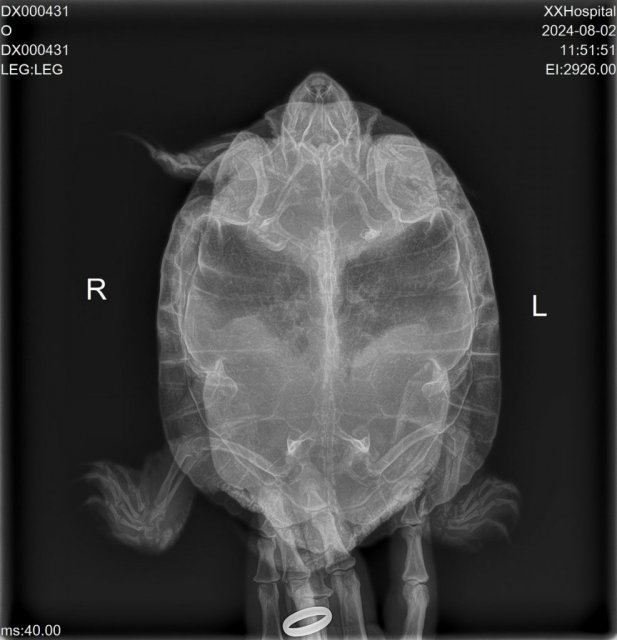

Консультанты moth Ваше имя: Мария Локация: Москва Опубликовано: 31 июля 2024 Консультанты Опубликовано: 31 июля 2024 @Алеся Панкова Дитрим точно колоть больше не нужно сейчас любой препарат, тем более в неверной дозировке, может в принципе её добить. И держать черепаху сейчас нужно вне аквариума, иначе опять утонет - посадите пока в контейнер без воды на влажные полотенца. Да, нужен рентген, чтобы проверить что с лёгкими и желудком, почему не смог всплыть. По фото у черепахи сильный провал панциря и отёкшие глаза - это признаки сильного авитаминоза и хронического дефицита кальция. Рентген если поедете делать - нужно минимум две проекции: под номером 1 и любая 2 или 3, но лучше 3.

Алеся Панкова Ваше имя: Газ Локация: Минская обл г Вилейка Опубликовано: 2 августа 2024 Автор Опубликовано: 2 августа 2024 Здравствуйте, все отменила.Сделала ренген.

Консультанты moth Ваше имя: Мария Локация: Москва Опубликовано: 2 августа 2024 Консультанты Опубликовано: 2 августа 2024 @Алеся Панкова если финансы позволяют - возьмите онлайн консультацию у любого ветеринара из списка https://cherepahi.ru/servisy/konsultatsii/ кроме Бойцовой, она сейчас долго отвечает. Из того, что я вижу - есть помутнение в лёгких (инфекция) и снижена плотность костей, нужно чтобы внимательно посмотрел именно врач и назначил правильное лечение. Если нет - напишите, я распишу лечение как я вижу, но в интересах черепахи обратиться именно ко врачу, т.к. тут случай очень серьёзный